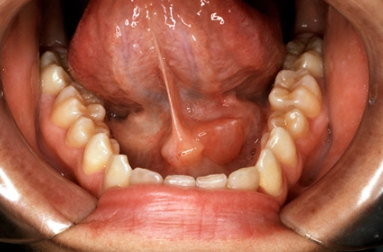

③ 타석증(침샘 결석)

침샘관 안에 돌(타석)이 생겨 침이 제대로 배출되지 않으면 반복적인 염증을 초래합니다. 타석 크기에 따라 저절로 배출되기도 하지만, 크거나 만성적인 경우 내시경적 제거 또는 수술이 필요할 수 있습니다.